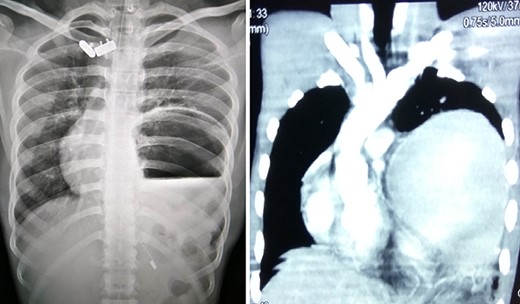

Chest X-ray and CT showing an elevated left hemi-diaphragm with a large sub-diaphragmatic air-fluid level.

A 19-year-old male with no known co-morbidities presented to the emergency department with 2-day history of severe upper abdominal pain and vomiting. He complained of similar episodes over the past 2 years, which used to get relieved spontaneously. On examination, the patient was tachycardic (110 bpm) with normal blood pressure and normothermic. The upper abdomen was asymmetrically distended, non-tender with a tympanic note. The laboratory investigations were within normal limits. Chest X-ray revealed markedly elevated (>4 cm) left hemi-diaphragm, huge gastric shadow with an air-fluid level and shift of mediastinum toward the right side (Fig. 1). Acute gastric volvulus was suspected based on the above finding, which was confirmed with contrast CT. Patient underwent initial laparoscopic evaluation, which was converted to open procedure. Intraoperatively, there was an organo-axial volvulus without any vascular compromise secondary to diaphragmatic eventration. It was de-rotated, decompressed and anterior abdominal wall suture gastropexy done. The freely mobile stomach was further reinforced with sham (trans-seromuscular) gastrojejunostomy. Left diaphragmatic eventration was plicated with polypropylene suture number 1 (Fig. 2) for which it required open conversion. Postoperative period was uneventful and discharged on Day 6. At 16-month follow-up, patient is doing absolutely fine.